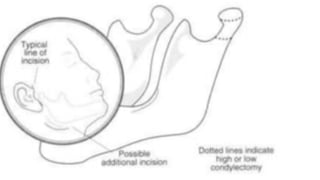

• CONDYLECTOMY is done by excision of the of the condyle head above the

attachment of the lateral pterygoid muscle.This allows free translation of the

condyle along the articular eminence.It may high or low depending on the

portion (either superior or inferior)of the condyle used.High condylectomy is a

more conservative approach. Condylectomy is the last option as it results in

facial and occlusal deformity.